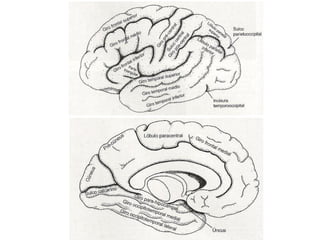

(1) Prosencéfalo

Cérebro

Tálamo

Hipotálamo

Hipófise

4º ventrículo

Sulco       Sulco

pré-central   central